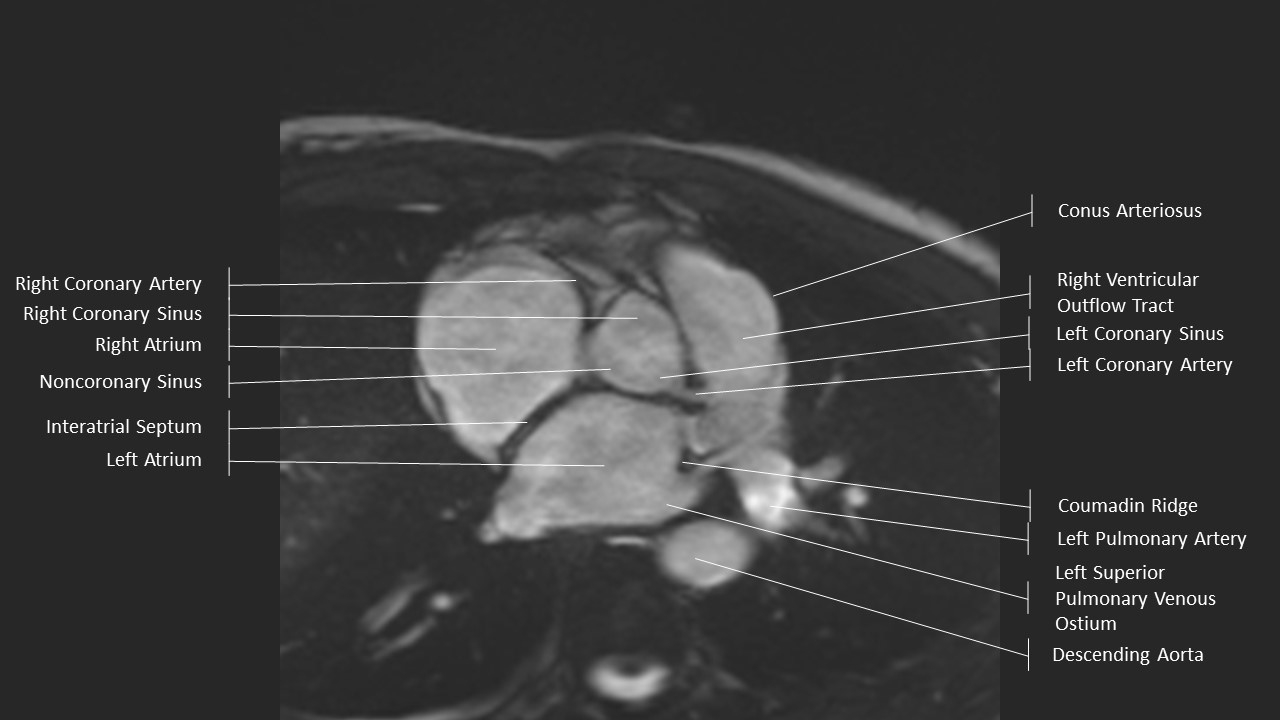

Aortic Root Series:

Sinuses of Valsalva

Aortic Root Series